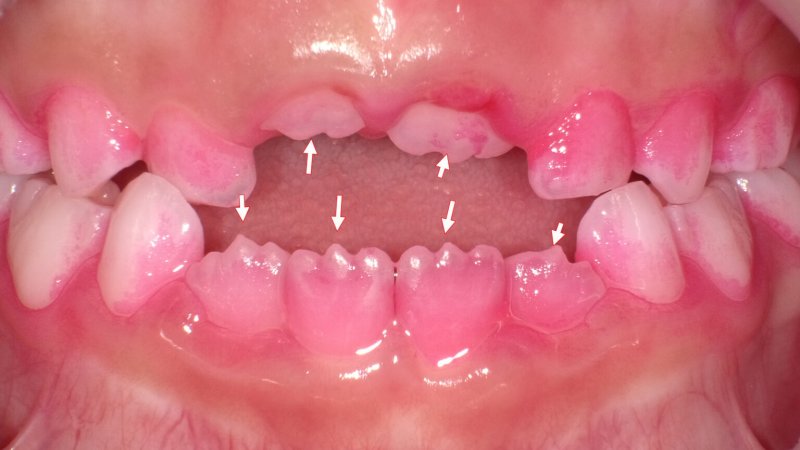

小児にみられる生理的なギザギザ(マメロン)

永久歯の萌出直後に認められる切縁の凹凸は「マメロン(切縁結節)」と呼ばれ、生理的な形態です。

咀嚼や咬合接触により自然に摩耗し、通常は数ヶ月から数年で平滑化します。疼痛や機能障害がなければ治療の必要はありません。